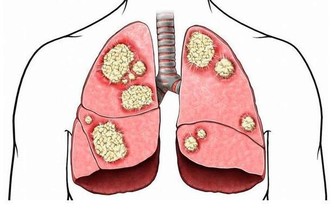

酒精被吸收到血液之後,首先會經肝臟分解為乙醛,這是一種對身體各組織細胞有著非常強的刺激作用的物質。

我們再來了解一下飲酒對肝臟方面的影響,肝細胞在乙醛的強烈刺激下會表現得非常興奮,也會合成更多包括甘油三酯、高密度脂蛋白等在內的脂肪,甘油三酯為大量積存在肝細胞當中,此時脂肪肝便發生了,長久以往會使肝細胞持續受到損傷。

過多的脂肪進入到血管之後,因乙醛損傷了血管內皮,而更容易沉積在血管的內皮之下,促進與加速了血管病變的發生。